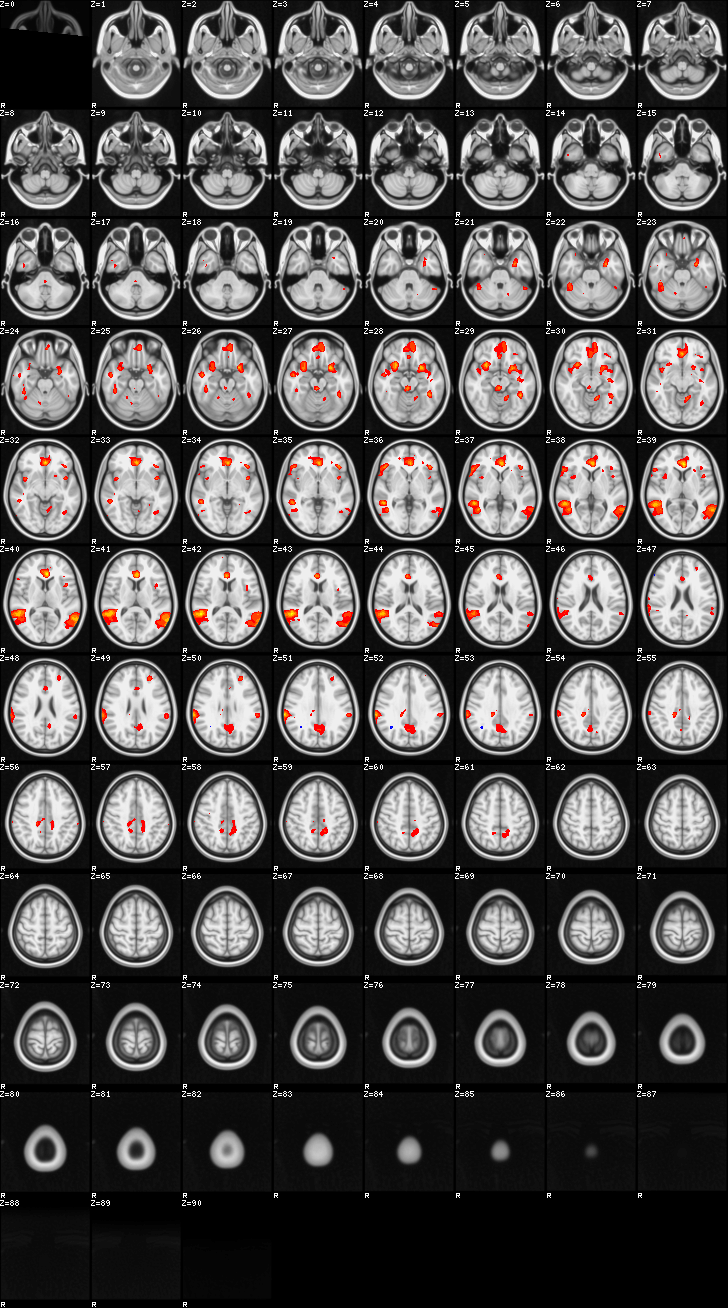

Mixed Effect (flame1)¶

ATM it is 26 subjects, 8 mm FWHM spatial (simple gaussian) smoothing, preliminary results only

Images thresholded abs value > 2.3 and colormap goes from 2.3 to 5 (red->yellow) or -2.3 to -5 (blue->lightblue)

00-FgtC¶